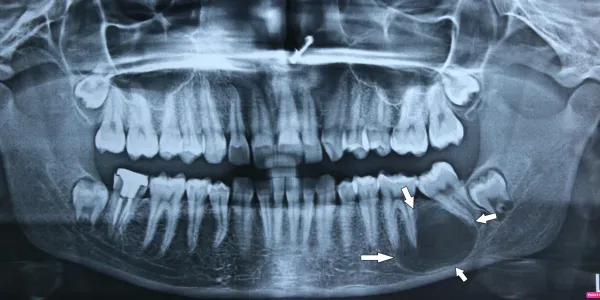

Jaw tumors and cysts include ameloblastoma, odontogenic keratocysts and dentigerous cysts. Most present as painless jaw swelling found on radiograph. Management ranges from enucleation for small cysts to segmental jaw resection with reconstruction plate for aggressive tumors.

Incidental finding on dental X-ray